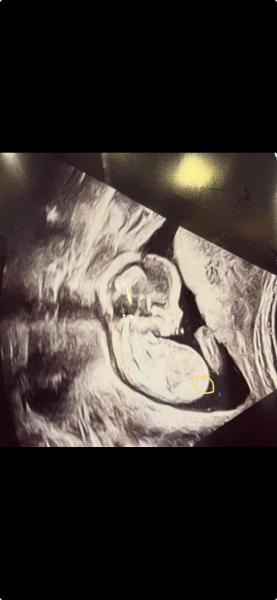

Könnten die 3 Striche auf das Geschlecht hindeuten oder ist das etwas anderes ? (habs mal eingekreist, sieht man kaum) Bild ist von 16+0 und Baby dreht den Rücken etwas zu uns.  Bei meiner Tochter damals hat man auch 3 Striche gesehen aber von einer anderen Position.  Liebe Grüße 🤗

Bild zu Was meint ihr ? 🩵🩷 - Schwanger - wer noch? Rund um die Schwangerschaft